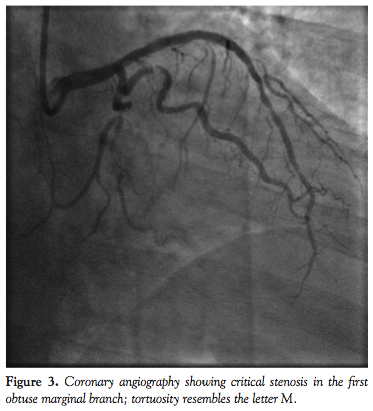

For the overall study group, there were no peri- or postprocedural MACEs. Mean fluoroscopic time was 25.3 ± 17.2 minutes and mean contrast volume was 203.1 ± 80.1 mL. Figures 1 through 8 illustrate our experiences with Integrity coronary stents in some of the “classical” tortuous coronary vessels.

One striking feature we observed about the Integrity coronary stent was that it conformed very well to the vessel wall (Figures 1-8). This is important, since it means the stent has sufficient radial strength to resist the elastic recoil of the media and can mold its shape along the contour of a curved segment with minimal vessel straightening and provide a large desired lumen. When the DES is implanted, excellent apposition of the struts on the vessel wall will ensure uniform delivery of the cytostatic drug to prevent neointimal hyperplasia. An in vitro conformability test15 has shown the Integrity DES to have better strut apposition and lower vessel wall stress when compared to other market-leading DESs. This has